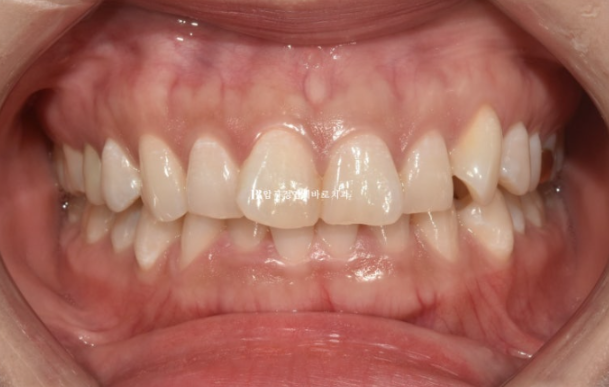

23.04

앞니 배열이 삐뚤합니다.

옆모습 분석에서는 앞니 각도가 정상이고 입술돌출이 크지 않아 사랑니 공간을 이용하며 돌출 개선을 소량만 도모하기로 했습니다.

대신 웃을 때 잇몸이 보이는 것도 같이 개선을 하기 위해서 앞니를 함입시키는 치료도 계획했습니다.

비발치 돌출입 교정은 통상 1년 6개월을 예상기간으로 봅니다.

클리피씨 교정 선택하고 진행했습니다.